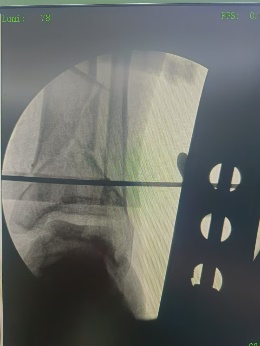

牽拉并透視